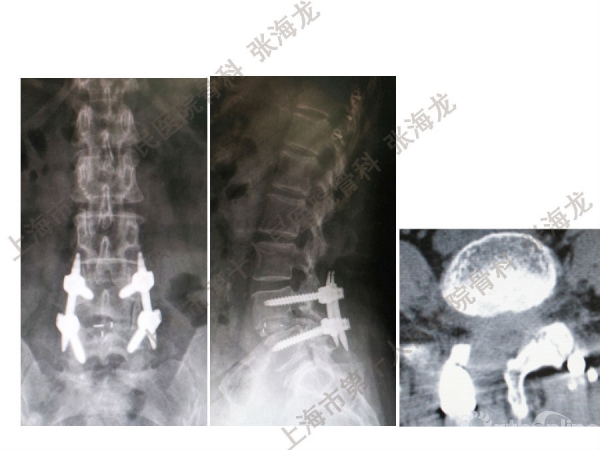

2008年3月至2010年8月,上海市第十人民医院骨科随访49例腰椎滑脱症(峡部裂型和退变型)患者,对比23例微创手术MIS-TLIF和26例开放手术治疗腰椎滑脱症的临床及影像学结果,进行了回顾性研究。

研究发现,Wiltse入路Mis-TLIF更直接的暴露峡部及关节突,对脊柱稳定性的影响较小;彻底松解辅助双重提拉复位Mis-TLIF,对于峡部裂型滑脱有较好的复位效果;对于峡部裂型滑脱,提拉复位在影像学参数上有一定优势;与原位融合相比,ODI.VAS.JOA无明显差异(样本量有限);对于退变性滑脱,单纯撑开椎间隙与原位融合可以获得较好疗效。